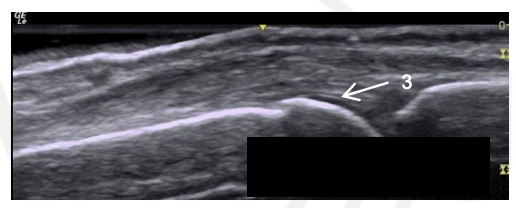

What is 3?

This is the interface sign in a normal MCP